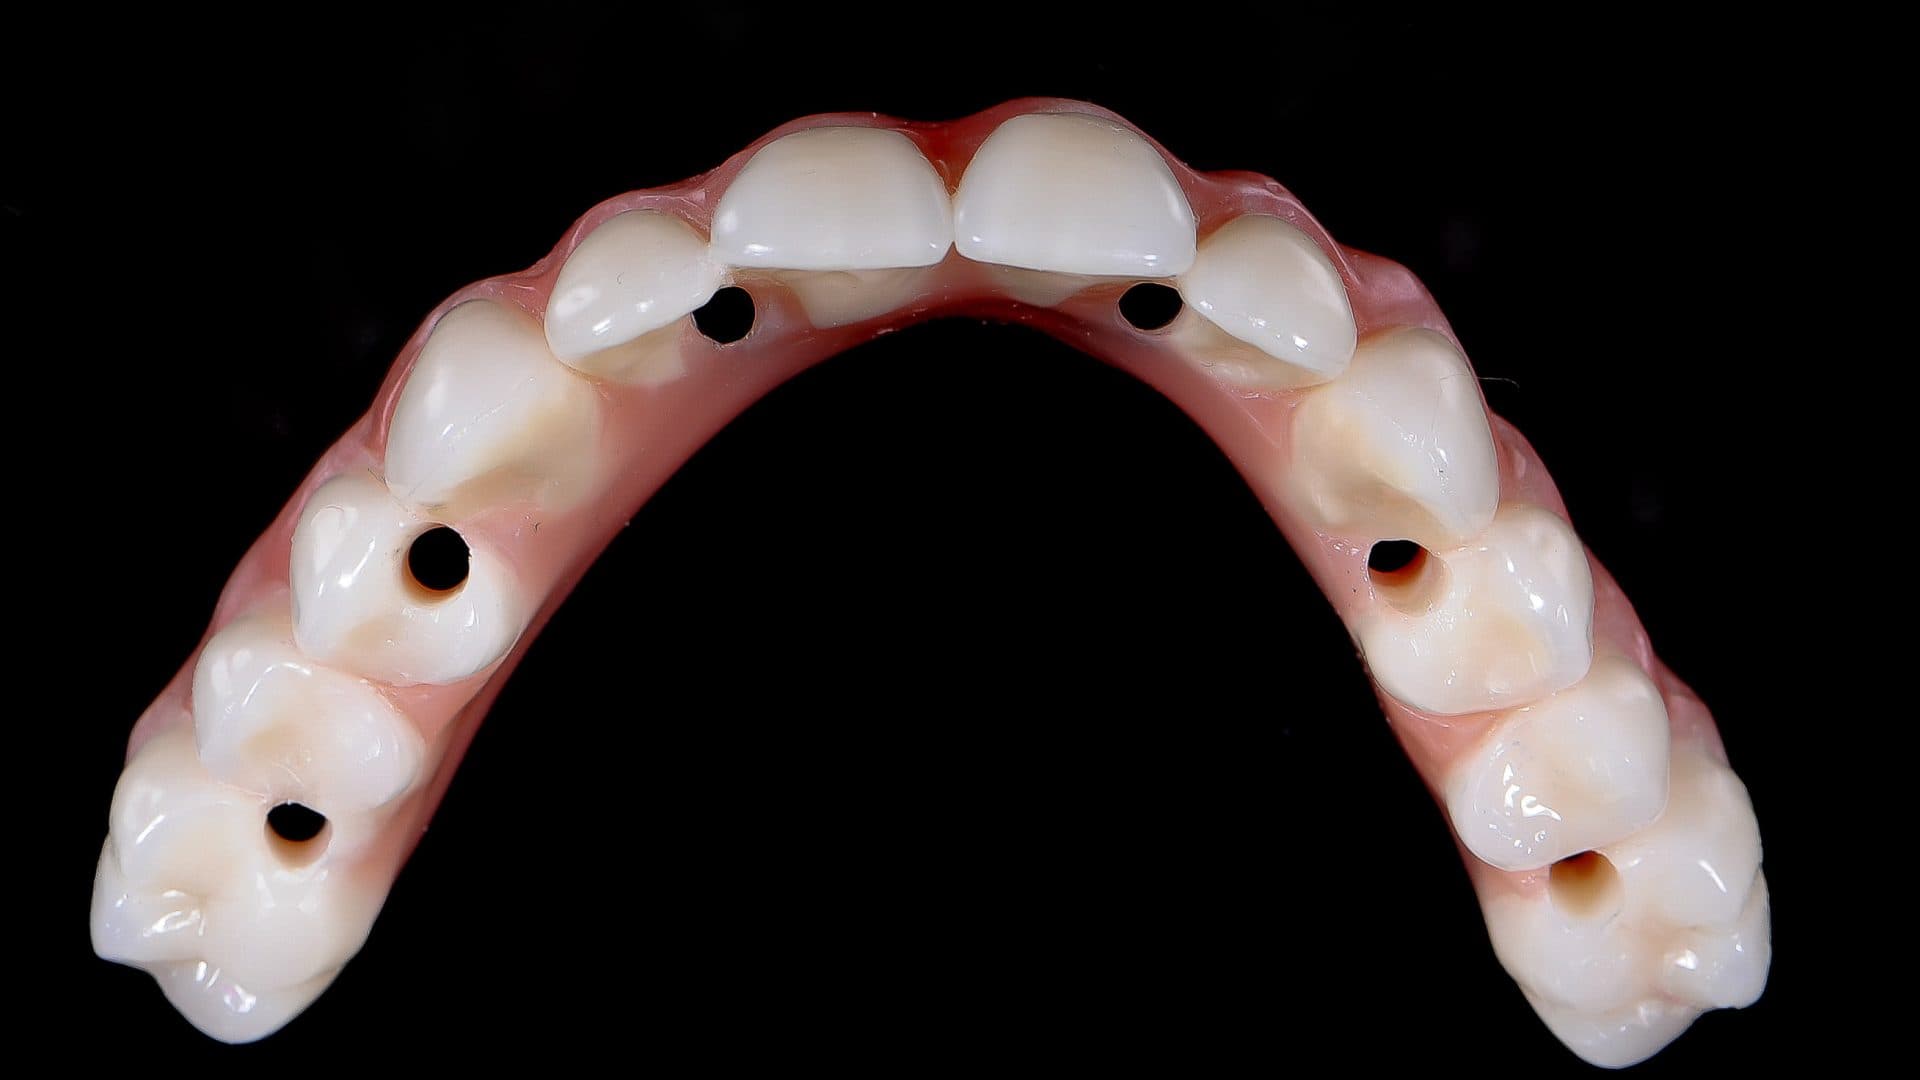

ii. The access holes for the screws are located near the edges of the front teeth and in the middle of the back teeth. Any deviation from this will severly affect level of comfort, speech, and also cleanability (See pictures);

Ideal Situation